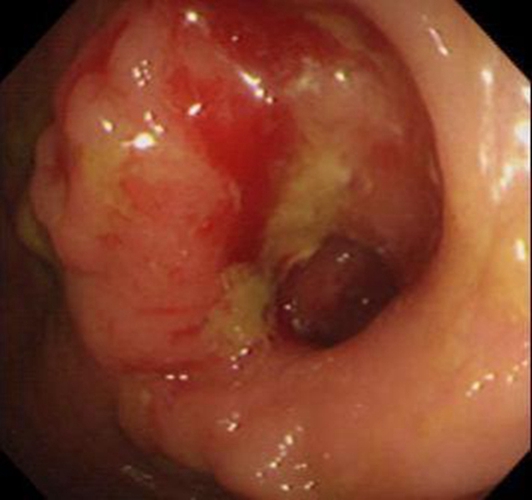

右半結腸癌潰瘍型常見臨床 特點